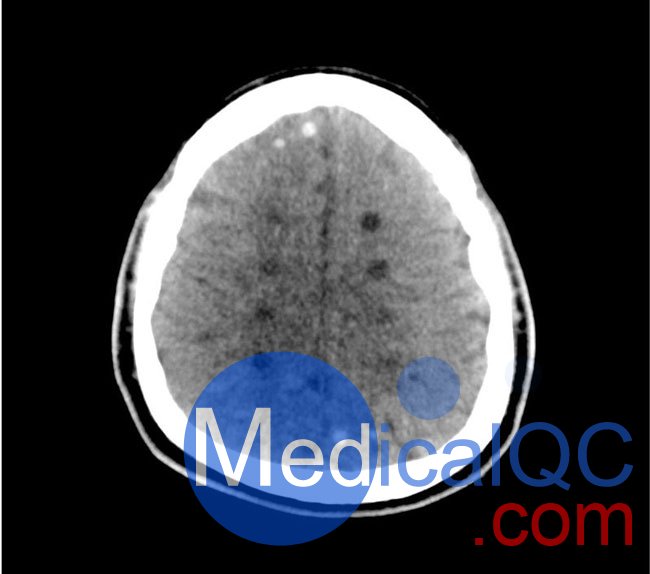

50-01頭部CT模體,50-01腦中風(fēng)頭部模體,50-01腦出血頭部模體模擬了具有中風(fēng)和出血模式的頭部。它覆蓋枕骨大孔的頂點(diǎn)。

卒中模式包括早期梗死的體征(大腦中動(dòng)脈高密度、基底神經(jīng)節(jié)消失)、急性和亞急性分水嶺梗死以及不同年齡的腔隙性梗死。

出血模式包括蛛網(wǎng)膜下腔出血、不同年齡的硬膜下出血、腦室內(nèi)出血和腦出血。

50-01頭部CT模體,50-01腦中風(fēng)頭部模體,50-01腦出血頭部模體診斷特征

中風(fēng)

高密度大腦中動(dòng)脈 (MCA) 和左側(cè)基底神經(jīng)節(jié)消失

中/后 (MCA/PCA) 和大腦前/中動(dòng)脈 (ACA/MCA) 區(qū)域的分水嶺梗死

8 個(gè)不同年齡的腔隙性梗死

出血

蛛網(wǎng)膜下腔出血(2個(gè)地區(qū))

不同年齡的硬膜下出血(3個(gè)地區(qū))

腦室內(nèi)出血(左側(cè)腦室)

腦出血(2 個(gè)丘腦,6 個(gè)皮質(zhì)下)

50-01頭部CT模體,50-01腦中風(fēng)頭部模體,50-01腦出血頭部模體影像效果圖: